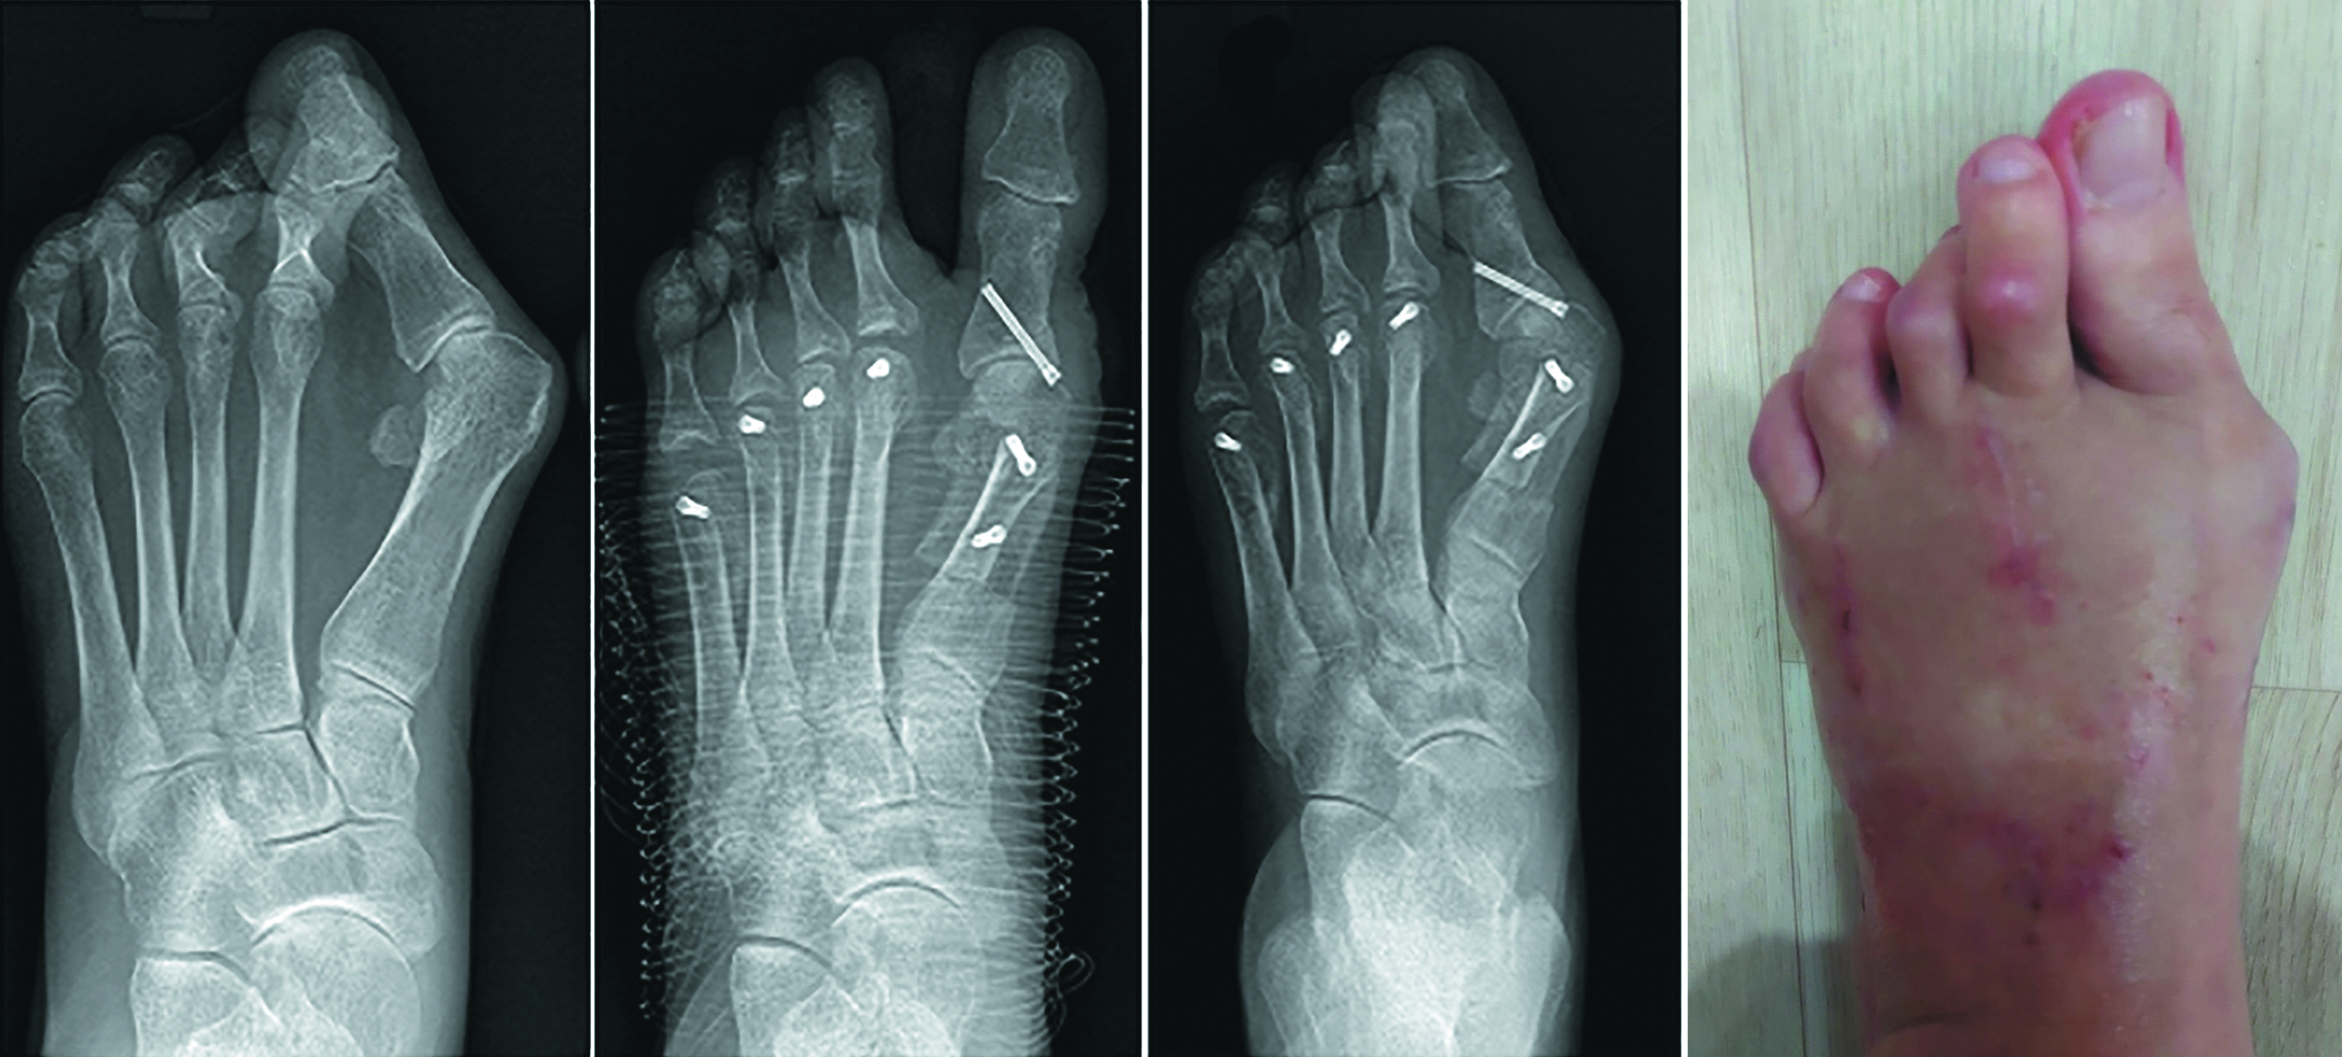

The formation of the false joint of the great toe was registered in one case, where we observed lack of consolidation in the site or arthrodesis after the removal of Kirschner's wires 8 weeks after the surgery (Fig. 2). We need to consider the intraoperative complications that the surgeons faced: they were associated with pronounced cystic reorganization of the head of the first metatarsal bone and the proximal phalanx of the first toe and the poor quality of bone tissue, which made it difficult to fix the achieved correction. Despite the complication, the female patient reported no pain or restrictions in her everyday life after the surgery. After JPS, no formation of false joints was observed.

Figure 2. A – postoperative X-ray; B – X-ray 8 weeks after GRS (false joint 1 MTP).

Рисунок 2. A – послеоперационная рентгенограмма; B – рентгенограмма через 8 недель после ГРО (ложный сустав 1 ПФС).